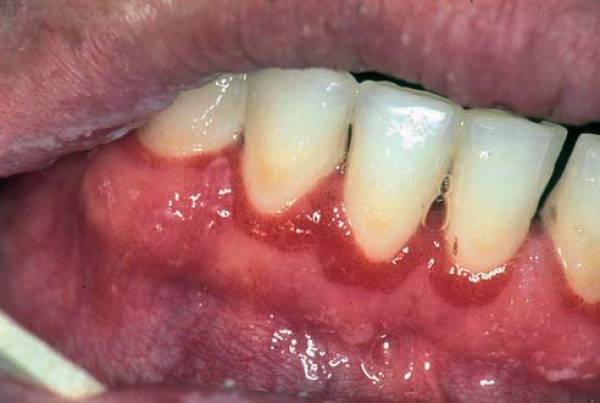

Фото 1. Воспаление десен – причиной может стать распространение бактерий от больных зубов во время операции.

В первом случае, во время операции по удаления зуба, врач мог случайно повредить нервное окончание или оставить в ранке осколок зуба. Если это произошло, рекомендуется повторно обратиться в больницу, для обнаружения точной причины неприятного последствия. Для устранения проблемы придётся прибегнуть к оперативному вмешательству.

Если причиной зуда и чувствительности стало воспаление слизистой, значит рядом с опустевшей лункой находится зуб, поражённый кариесом. Во время операции по удалению восьмёрки врач обязательно санирует полость рта, но это не даёт гарантии того, что болезнетворные бактерии не попадут в ранку.

Важно! Чтобы избежать этой проблемы, после операции нужно как можно тщательней следить за чистотой полости рта.